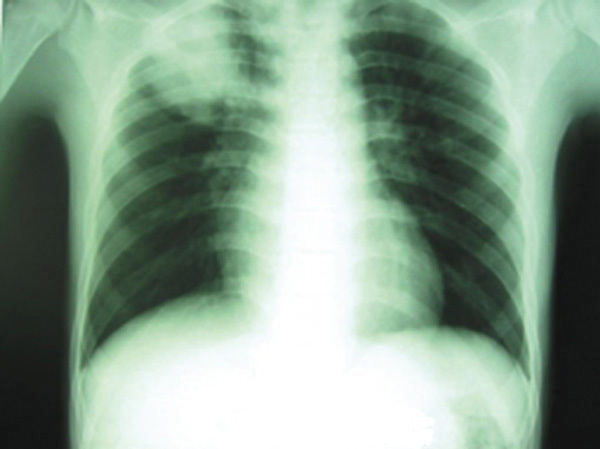

©La Revue du Praticien Radiographie de thorax de face. Condensation alvéolaire du lobe supérieur droit due à une pneumonie à pneumocoque.